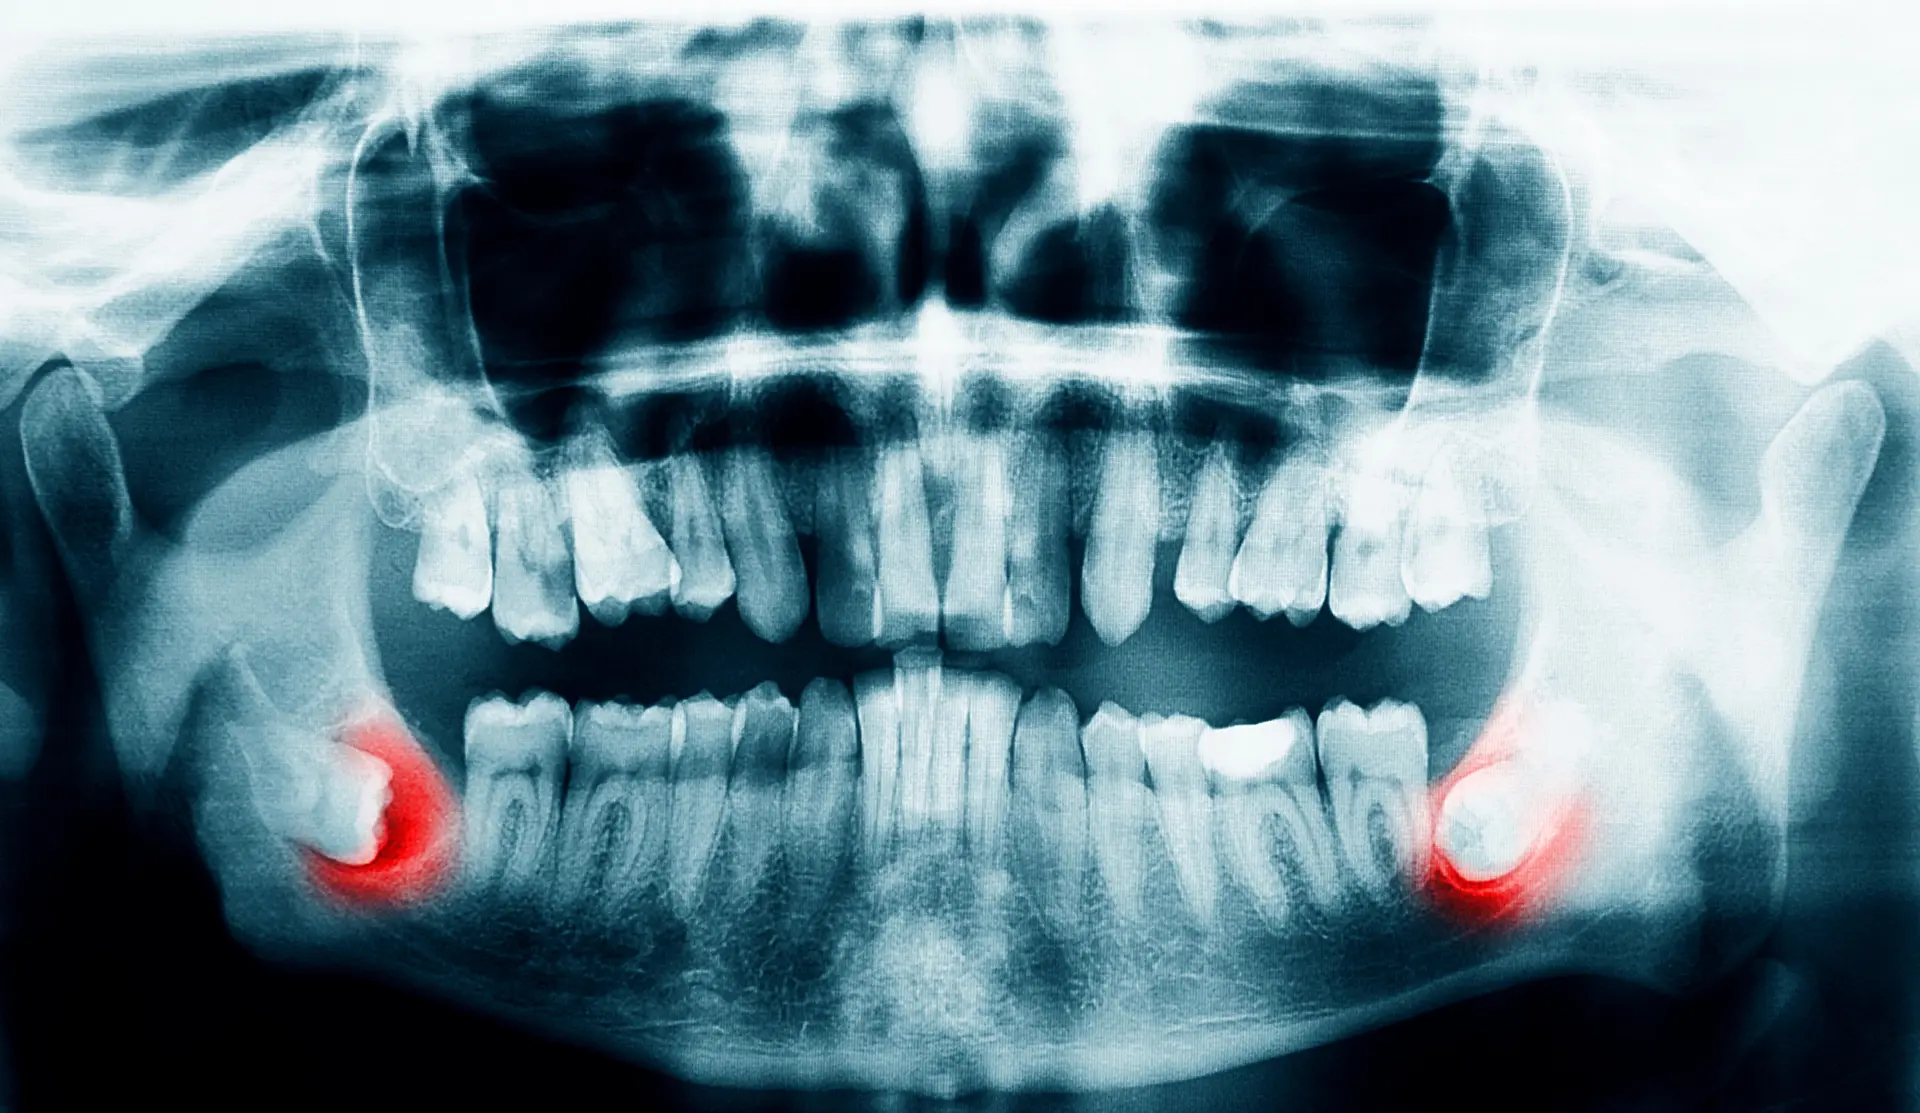

Our treatment plan will be determined based on your medical history and any relevant x-rays taken from your general dentist. We may need to take additional x-rays to ensure we have a complete view of your oral health. We will then create a personalized plan tailored to your unique needs and go over sedative options for maximum comfort.

There are many reasons why wisdom teeth removal may be necessary. This includes wisdom teeth growing in at the wrong angle. They can grow sideways, partially erupt, or even become trapped underneath the gum and bone. Impacted wisdom teeth can take many positions in the bone as they try to find a pathway to successfully erupt. All of these reasons make wisdom teeth removal necessary to preserve your oral health.